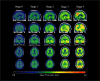

A biological research framework to define Alzheimer' disease with dichotomized biomarker measurement was proposed by National Institute on Aging-Alzheimer's Association (NIA-AA). However, it cannot characterize the hierarchy spreading pattern of tau pathology. To reflect in vivo tau progression using biomarker, we constructed a refined topographic 18F-AV-1451 tau PET staging scheme with longitudinal clinical validation. Seven hundred and thirty-four participants with baseline 18F-AV-1451 tau PET (baseline age 73.9 ± 7.7 years, 375 female) were stratified into five stages by a topographic PET staging scheme. Cognitive trajectories and clinical progression were compared across stages with or without further dichotomy of amyloid status, using linear mixed-effect models and Cox proportional hazard models. Significant cognitive decline was first observed in stage 1 when tau levels only increased in transentorhinal regions. Rates of cognitive decline and clinical progression accelerated from stage 2 to stage 3 and stage 4. Higher stages were also associated with greater CSF phosphorylated tau and total tau concentrations from stage 1. Abnormal tau accumulation did not appear with normal β-amyloid in neocortical regions but prompt cognitive decline by interacting with β-amyloid in temporal regions. Highly accumulated tau in temporal regions independently led to cognitive deterioration. Topographic PET staging scheme have potentials in early diagnosis, predicting disease progression, and studying disease mechanism. Characteristic tau spreading pattern in Alzheimer's disease could be illustrated with biomarker measurement under NIA-AA framework. Clinical-neuroimaging-neuropathological studies in other cohorts are needed to validate these findings.